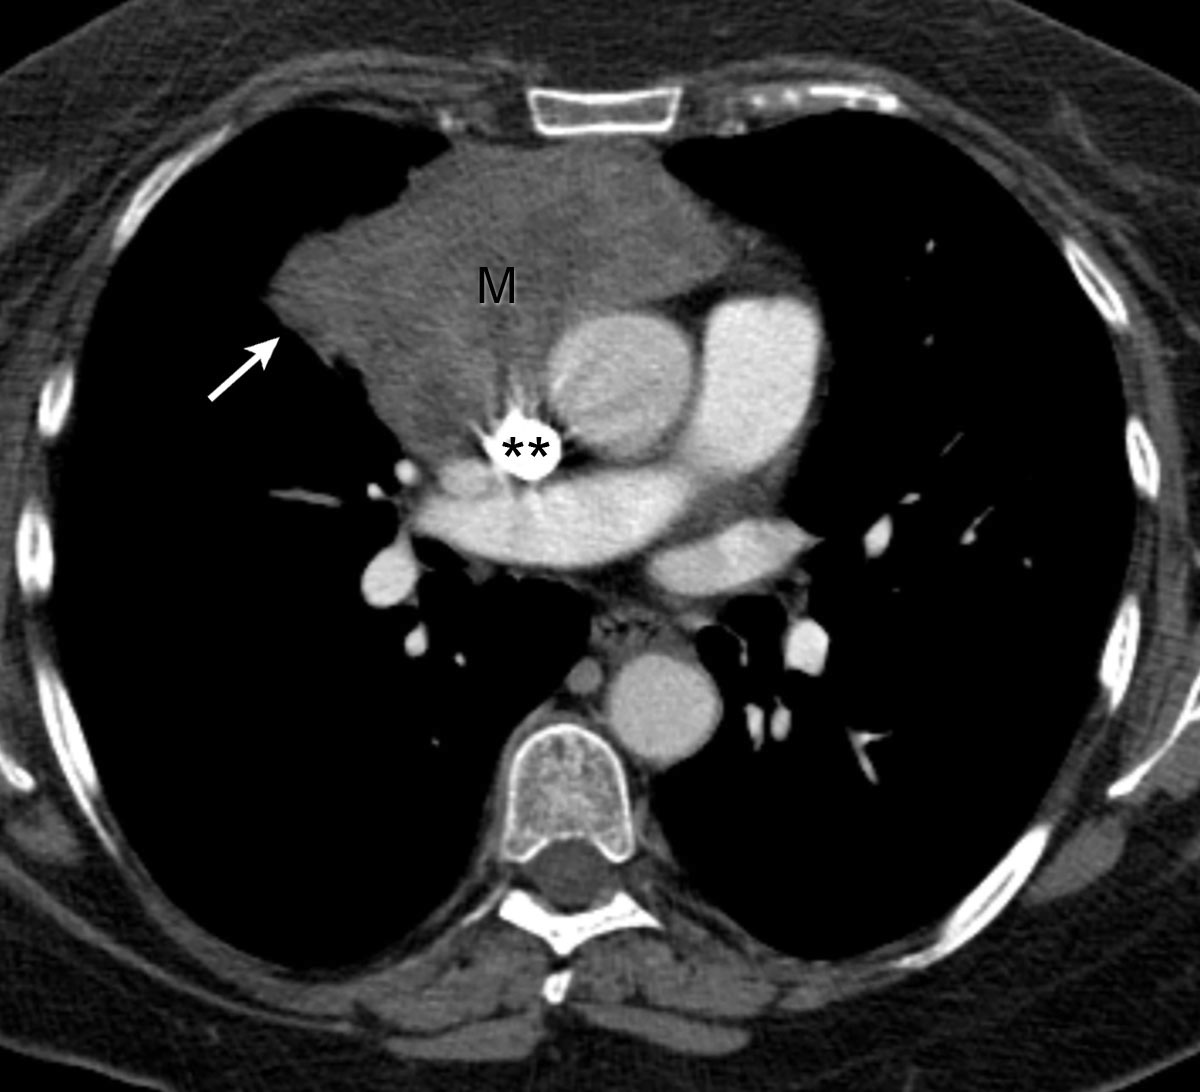

The value of diffusionweighted and dynamic contrastenhanced imaging

The value of diffusionweighted and dynamic contrastenhanced imaging Thymic Neoplasm Icd 10 Primary or metastatic malignant neoplasm involving the thymus. C37 is a billable diagnosis code used to specify a medical diagnosis of malignant neoplasm of thymus. Primary or metastatic malignant neoplasm involving the thymus. Thymoma is a tumor originating from the epithelial cells of the thymus. This category includes malignant thymomas, thymic lymphomas, primary. The icd code c37 is used to. Thymic Neoplasm Icd 10.